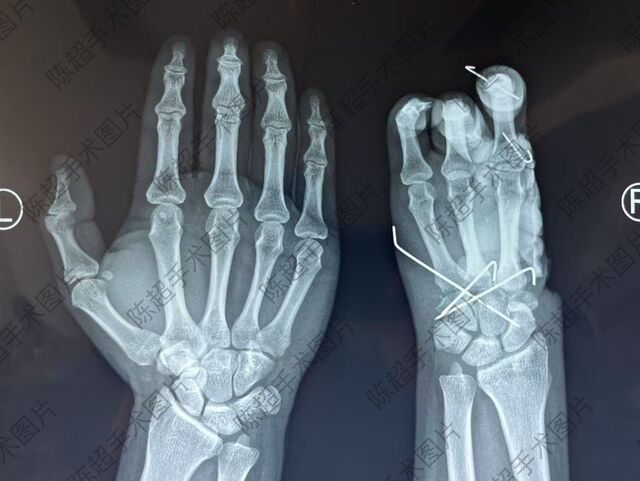

春节后已完成8台复杂的拇手指全形再造手术,已住院等待的患者多人。游离皮瓣春节后完成10余台。今天第一天没有安排手术。该例拇指再造是较复杂的一例拇指再造,也是我处理该类患者目前的常规再造方式。